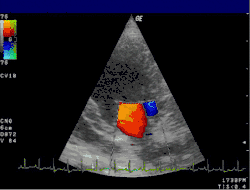

Цветовое доплеровское картирование (ЦДК)

Основано на кодировании в цвете значения доплеровского сдвига излучаемой частоты. Методика обеспечивает прямую визуализацию потоков крови в сердце и в относительно крупных сосудах. Красный цвет соответствует потоку, идущему в сторону датчика, синий — от датчика. Темные оттенки этих цветов соответствуют низким скоростям, светлые оттенки — высоким. Недостаток: невозможность получения изображения мелких кровеносных сосудов с маленькой скоростью кровотока. Достоинства: позволяет оценивать как морфологическое состояние сосудов, так и состояние кровотока по ним.

Эхокардиография (ЭхоКГ) — это ультразвуковая диагностика заболеваний сердца. В этом исследовании оцениваются размеры сердца и его отдельных структур (желудочки, предсердия, межжелудочковая перегородка, толщина миокарда желудочков, предсердий и т. д.), наличие и объём жидкости в полости перикарда, состояние клапанов сердца, а также, в доплеровском режиме, кровоток в сердце и магистральных сосудах. С помощью специальных расчетов и измерений эхокардиография позволяет определять массу миокарда, сократительную способность сердца (фракцию выброса, сердечный выброс и др.). Обычно ЭхоКГ проводится через грудную клетку (трансторакально), также существует чреспищеводная ЭхоКГ (ЧП-ЭхоКГ), когда специальный эндоскопический датчик помещается в пищевод. ЧП-ЭхоКГ позволяет лучше рассмотреть сердце, так как датчик располагается к сердцу ближе, чем при обычной ЭхоКГ и поэтому становится возможным использовать датчик с более высокой частотой ультразвука, что повышает разрешающую способность изображения. Также существуют специальные высокочастотные интраоперационные датчики, которые помогают во время операций на сердце.

4D-ЭхоКГ представленная на изображении, позволяет получать живое 3D-изображение сердца, то есть в реальном времени, что может быть также полезно, для проведения данной методики требуется специальный 4D-датчик.